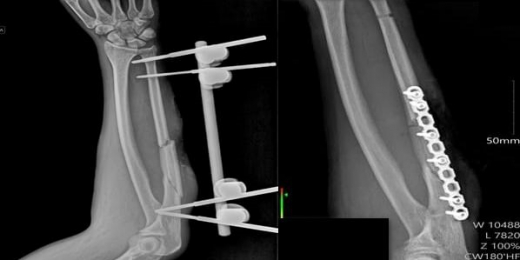

Пострадавший поступил в медучреждение с переломом локтевой кости и большой поверхностной раной. Лечение проводили в три этапа. Сначала хирурги провели первичную обработку и установили аппарат внешней фиксации, чтобы стабилизировать сломанную кость.

На заключительном этапе, через три недели, травматологи-ортопеды выполнили открытую репозицию отломков кости и провели погружной остеосинтез — зафиксировали перелом пластиной и винтами. Врачам удалось полностью восстановить анатомию и функции руки. Пациента уже выписали из стационара в удовлетворительном состоянии.